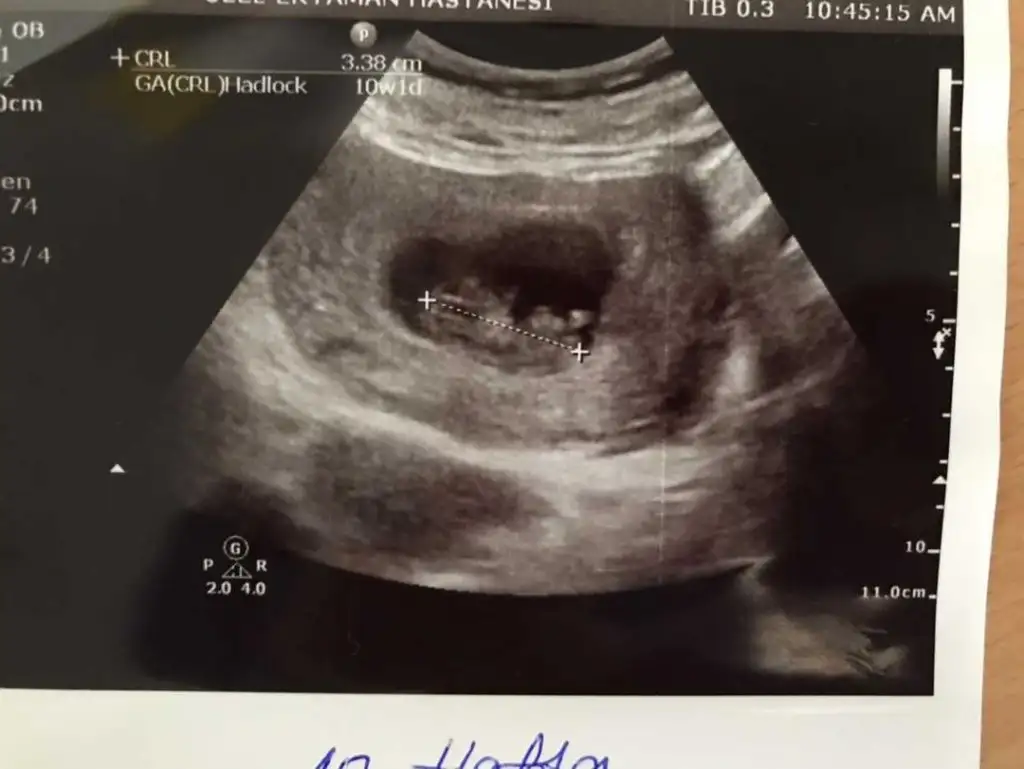

Merhaba arkadaşımın ultrason görüntüsüne bakar mısınız? 10. Hafta ve 12. Hafta ultrasonları.Teşekkürler

• 7FF8643E-BB02-4391-8D0B-2E1F0B581712.webp

7FF8643E-BB02-4391-8D0B-2E1F0B581712.webp

23,5 KB · Görüntüleme: 101

• 014BC34E-EE88-45F6-AFA3-2832026F3BE4.webp

014BC34E-EE88-45F6-AFA3-2832026F3BE4.webp

10 KB · Görüntüleme: 90